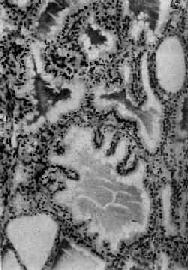

图15-7 毒性甲状腺肿 滤泡增生,有的扩大,上皮呈立方或高柱状,并乳头状突起。滤泡腔内胶质稀薄,周边有大小不等空泡 除甲状腺病变外,全身淋巴组织增生,胸腺肥大和脾肿大;心脏肥大、扩大,心肌可有灶状坏死及纤维化;肝细胞脂肪变性,空泡变性,甚至可有坏死和纤维增生。部份病例有眼球突出,其原因是眼球外肌水肿及淋巴细胞浸润;球后脂肪纤维组织增生,淋巴细胞浸润及大量氨基多糖积聚而形成的粘液水肿,目前认为系自家免疫反应所引起。

二、毒性甲状腺肿毒性甲状腺肿(toxic goiter)是具有甲状腺毒症的甲状腺肿。甲状腺毒症(thyrotoxicosis)是由于血中甲状腺素过多作用于全身组织所引起的综合征,其原因:①90%为甲状腺功能亢进,即甲状腺素的合成及分泌增多,如毒性甲状腺肿、毒性腺瘤、毒性结节性甲状腺肿;②甲状腺素释放增多,如某些类型的甲状腺炎;③极少数情况见于垂体促甲状腺细胞腺瘤或下丘脑促甲状腺释放激素的增多,引起继发性甲状腺功能亢进。 毒性甲状腺肿患者年龄常在30~40岁,女性发病比男性高4倍或更高。临床主要表现为甲状腺肿大,甲状腺功能亢进引起的代谢增高、心悸、多汗、多食、消瘦等症状,约有1/3伴有眼球突出,故又称为突眼性甲状腺肿(exophthalmic goiter)。 【病因和发病机制】 病因虽不太清楚,但已有以下证据说明本病为自身免疫性疾病:①与桥本甲状腺炎有许多相似之处,如血中球蛋白增高,并有多种抗甲状腺抗体;常与其他自身免疫性疾病如重症肌无力、血小板减少性紫癜、溶血性贫血等合并发生;②在诸多的抗各种甲状腺成分的抗体中,最重要的是能与TSH受体结合的自身抗体。因为具有类似TSH的作用,其中可分两种,一种是能促进甲状腺素分泌的甲状腺刺激免疫球蛋白(thyroid-stimulating immunoglobulins,TSI),另一种是促进滤泡上皮生长的甲状腺生长刺激免疫球蛋白(thyroid growth-stimulating immunoglobulins,TGI);③本病有家族性素质,在西方已证明在患者及其亲属中HLA-DR3分布频率高,提示有遗传基因素质。有人推测HLA-DR3人群中抑制性T细胞功能是有基因缺陷的,因而辅助性T细胞增强,使自身免疫抗体生成增多。 【病变】 肉眼观,甲状腺对称性弥漫肿大,一般为正常的2~4倍,质较软,切面灰红,胶质含量少。镜下,以滤泡增生为主要特征,滤泡大小不等,以小型滤泡为主。小型滤泡上皮呈立方形,大型滤泡上皮多为高柱状,常向腔内形成乳头状突起。滤泡腔内胶质少而稀薄,胶质的周边部即靠近上皮处出现大小不等的空泡,有的滤泡内甚至不见胶质。间质中血管丰富,显著充血,有多量淋巴细胞浸润并有淋巴滤泡形成(图15-7)。经碘治疗的病例,由于碘能阻断含甲状腺素胶质的分解和促进胶质的储存,故胶质增多变浓,上皮增生受抑制,间质充血减轻,淋巴细胞也减少。与此相反,经硫脲嘧啶等阻断甲状腺素合成的药物治疗者,由于血中TSH代偿性增加,故滤泡增生更明显,上皮呈高柱状,胶质更稀少甚至消失。